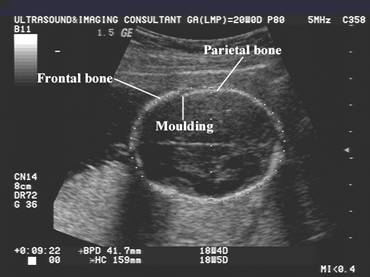

Moulding and overlap of the cranium sutures may occur in:

Severe oligohydramnios.

Premature rupture of membranes.

Extrinsic transducer pressure.